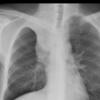

free air

Date: 01/12/2015

Views: 3810